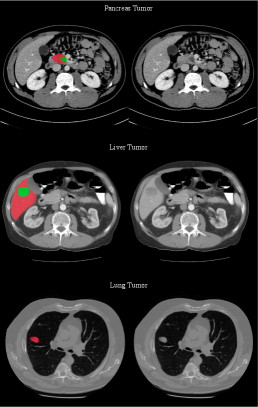

Refer to caption

Figure 6: The 5-fold averaged DSC of data augmentation experiments using synthetic data across 5 tumor types. The percentage of relative improvement compared to Real Only experiments is shown in green above each bar plot. All reported improvements are significant under the Wilcoxon signed rank test.

One of the critical applications of generative models in medical imaging is data augmentation for training deep learning models. To assess the effectiveness of synthetic images in improving model performance, especially for rare medical conditions, we integrate synthetic data generated by MAISI into a standard training pipeline and evaluate it across five tumor types. Specifically, we employ the Auto3DSeg222https://monai.io/apps/auto3dseg pipeline—an auto-configuration solution for training medical image segmentation models—to train models on the MSD Task03 [antonelli2022medical] (liver tumor), Task06 [antonelli2022medical] (lung tumor), Task07 [antonelli2022medical] (pancreas tumor), Task10 [antonelli2022medical] (colon tumor), and an in-house bone lesion dataset. We conduct experiments by training segmentation models either using only real data (referred to Real Only in Fig. 6) or by incorporating synthetic data from different models, thereby demonstrating the impact of synthetic data on data augmentation. To ensure robustness, we performed 5-fold cross-validation and reported the average Dice Similarity Coefficient (DSC) on the testing set across the five folds.

As discussed in Sec.3.3, the integration of ControlNet [zhang2023adding] introduces a flexible mechanism in MAISI, enabling the incorporation of task-specific conditions. To illustrate its versatility, we trained ControlNet [zhang2023adding] for two distinct tasks aimed at generating synthetic data for augmentation purposes. The first task (denoted as MAISI CT Generation in Fig. 6) is conditional generation from segmentation masks of 127 anatomical structures, including the five tumor types mentioned earlier. This approach allowed us to generate synthetic data by augmenting real patient tumor masks corresponding to each tumor type. The second task (denoted as MAISI Inpainting in Fig. 6) involves training a tumor inpainting model designed to simultaneously support liver, pancreas, and lung tumors, following the setting in[chen2024towards]. The tumor inpainting model requires a function to simulate tumor masks for adding synthetic tumors into healthy patient data. However, simulating tumors with irregular shapes, such as bone lesions and colon tumors, poses significant challenges. For a comparative analysis, we benchmark against the state-of-the-art tumor synthesis method, DiffTumor [chen2024towards], using their released model333https://github.com/MrGiovanni/DiffTumor which supports liver and pancreas tumors among five tumor types in our experiments.

Results shown in Fig. 6(a)\sim(e) indicate prominent improvements in DSC scores across all tumor types when incorporating synthetic data from our two augmentation tasks. Specifically, the MAISI CT Generation results in an average DSC improvement of 4% across the five tumor types. The MAISI Inpainting demonstrated a more substantial average improvement of 6.5% in DSC for liver, lung, and pancreas tumors, performing comparably or better than the DiffTumor [chen2024towards], which trains dedicated synthesis models for each tumor type. Additionally, we conduct an out-of-distribution evaluation by testing tumor segmentation models trained on MSD Task03 [antonelli2022medical] on 303 liver tumor samples from MSD Task08 [antonelli2022medical]. As shown in Fig. 6(f), models incorporating synthetic data consistently show greater relative performance improvements compared to those evaluated within their original training dataset in Fig. 6(b). These findings underscore the effectiveness of synthetic data as a powerful augmentation strategy to bolster the generalizability of segmentation models. More ablation studies and visualization of synthetic data can be found in Supplementary Sec. C.